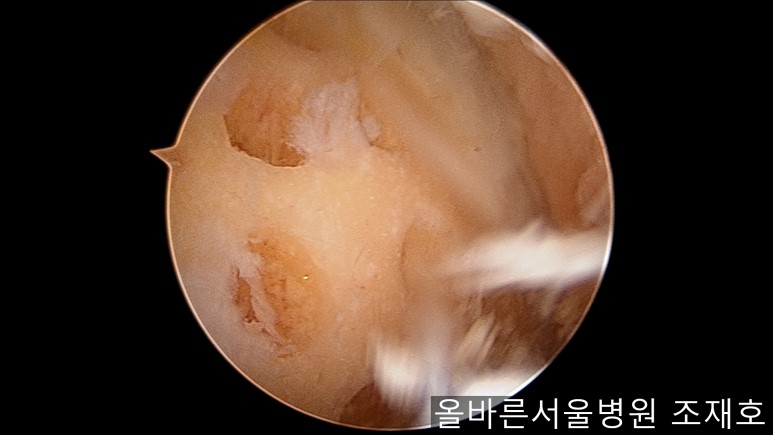

通过关节镜图像可看到:由于内侧股骨髁软骨损伤骨头已经显露出来。

胫骨上端的软骨损伤严重,也露出了骨头。

正是缺失软骨的部位碰到一起,引发剧烈疼痛,腿部逐渐变形。